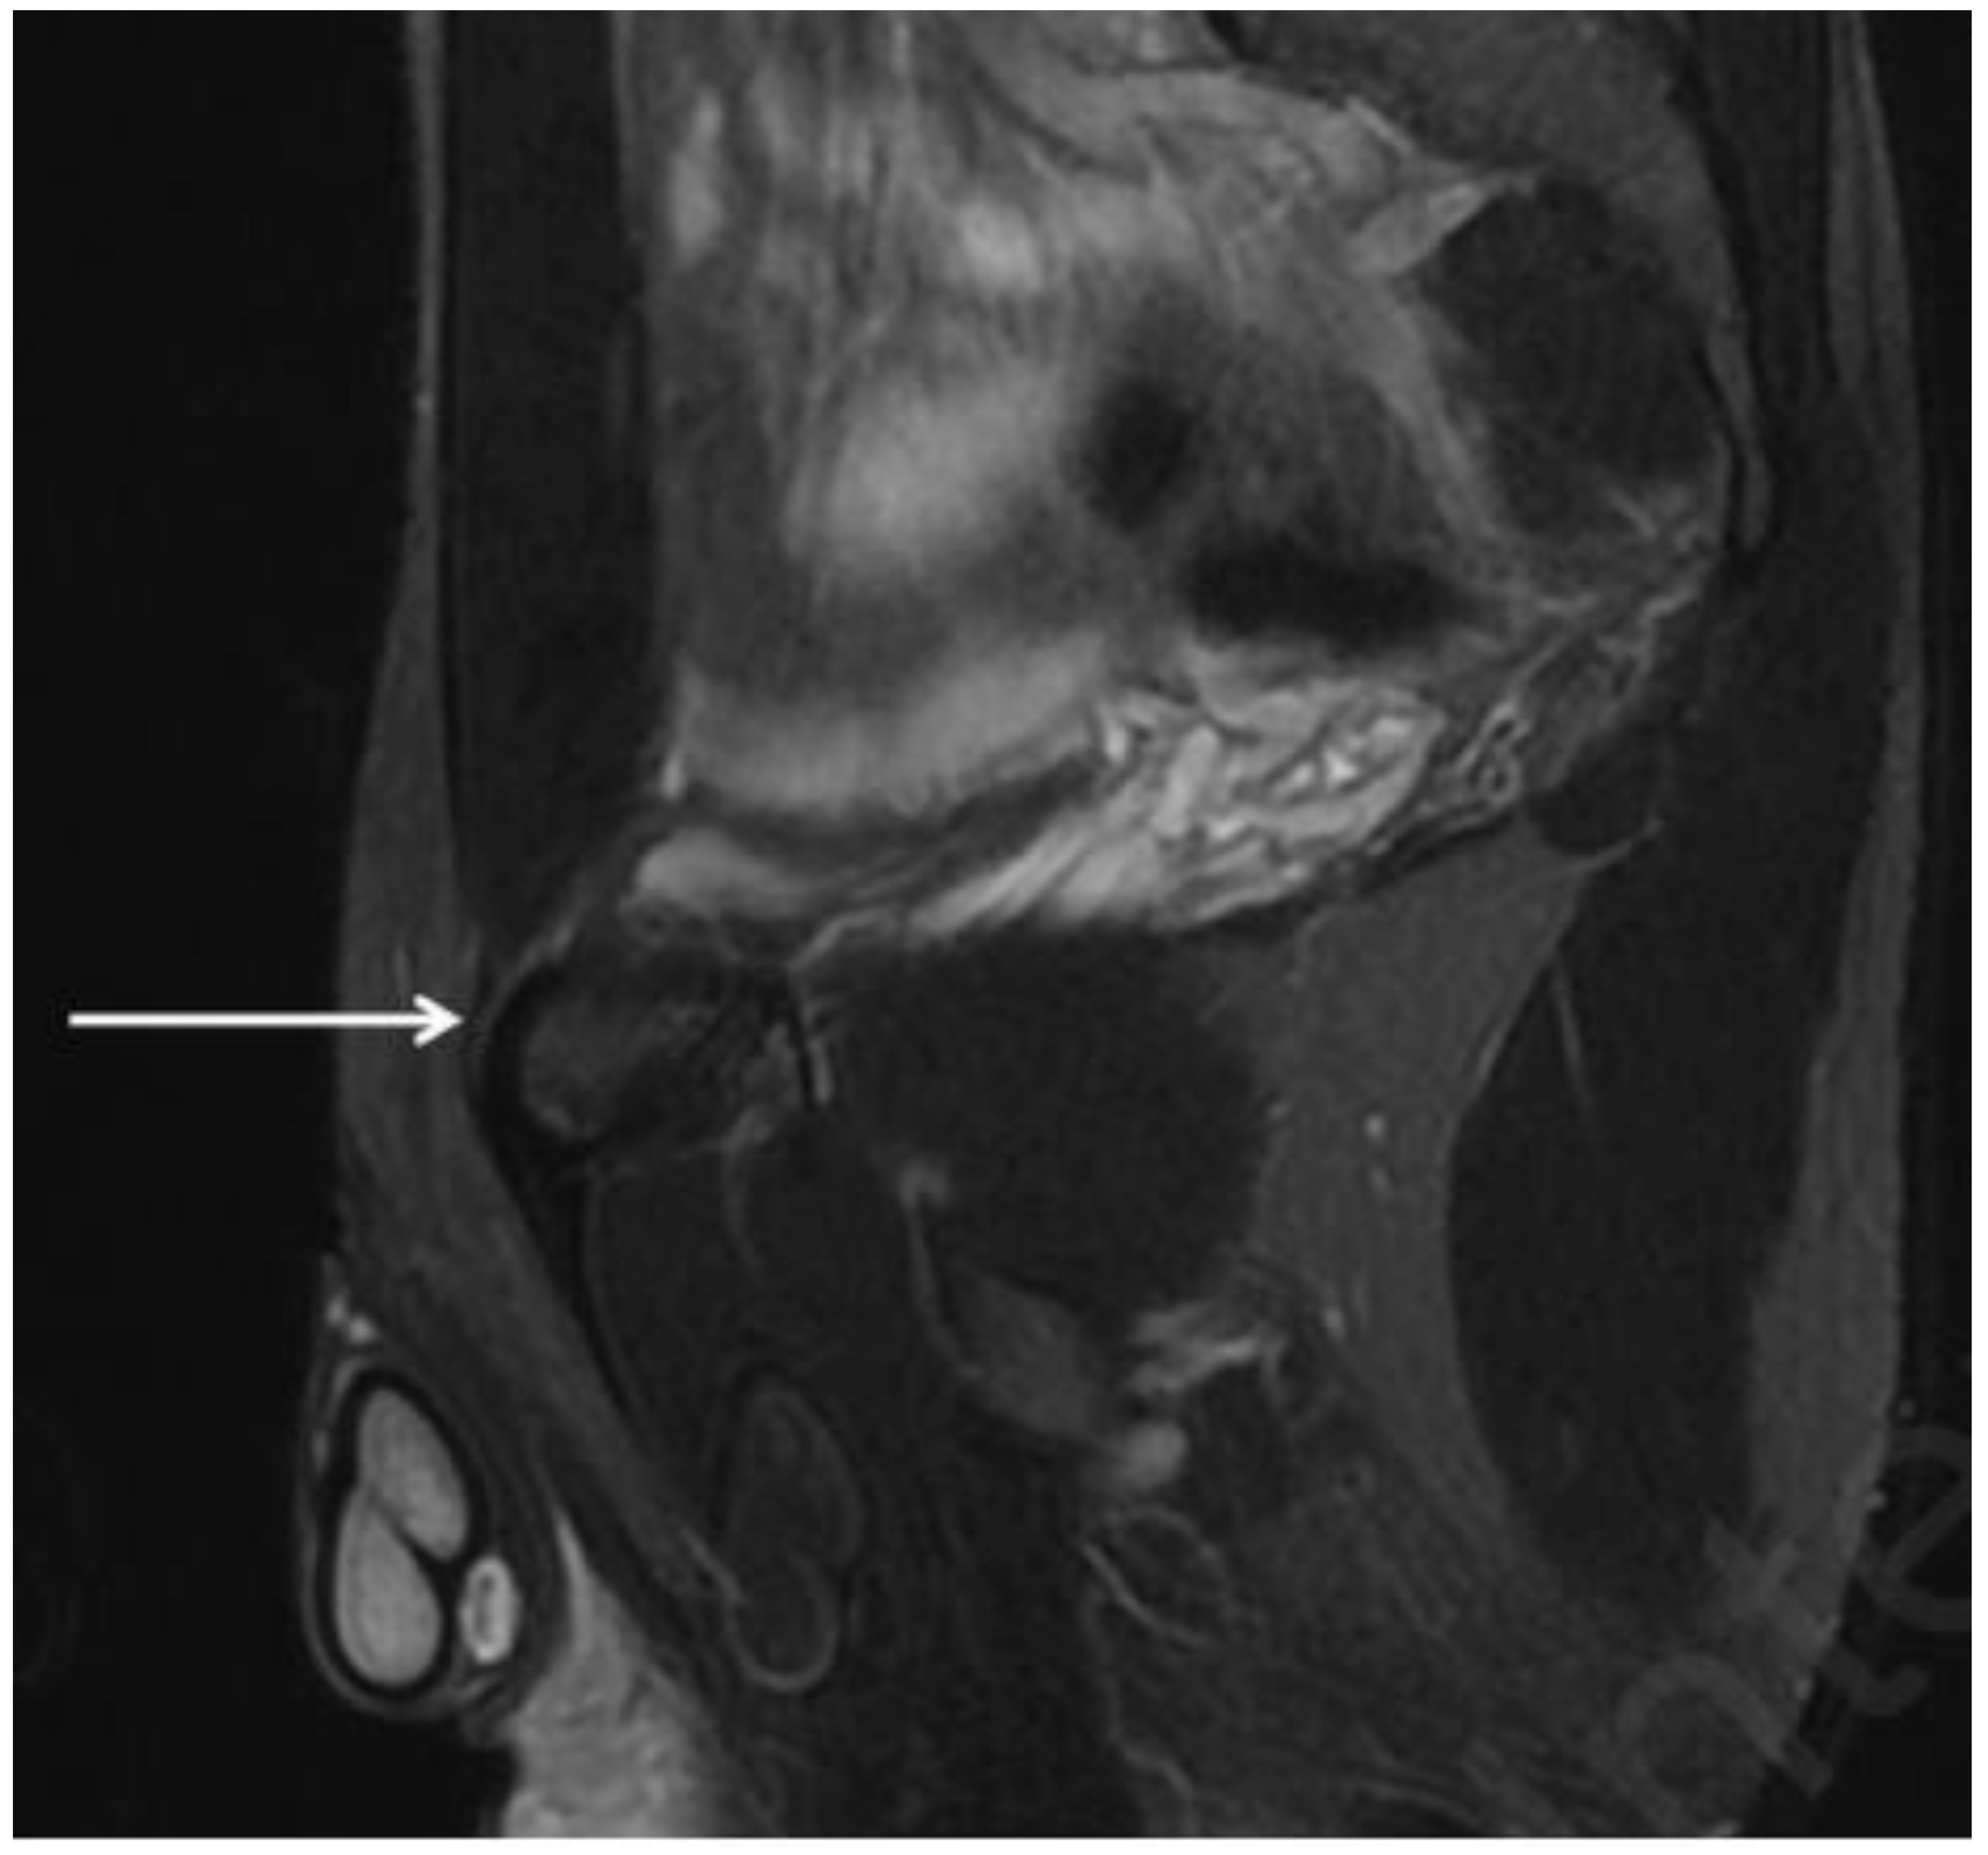

| Obturator hernia | Coronal and axial T1- and PD-weighted sequences | Protrusion of fat through the foramen between the pectineus and obturator externus muscles. Very important evaluation of the comparison for symmetry with the contralateral canal. |